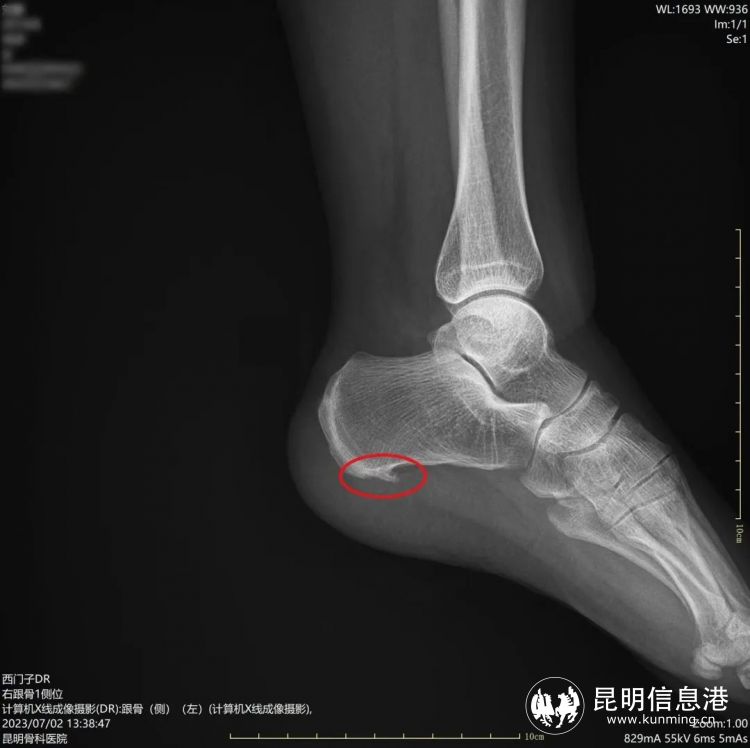

術(shù)前骨刺明顯

“經(jīng)檢查發(fā)現(xiàn)劉女士不僅左足跟有跟骨骨刺,雙足還有足底筋膜炎,本次微創(chuàng)手術(shù)只需在患者足內(nèi)側(cè)跟骨前結(jié)節(jié)處兩側(cè)各取一個0.2-0.5cm的小孔,建立鏡下手術(shù)工作通道,就能在可視下磨除跟骨骨刺,筋膜松解,處理炎癥組織。”昆明骨科醫(yī)院手足顯微外科主任李海波介紹說,這種新型的微創(chuàng)治療手段對比起傳統(tǒng)的治療來講有很大的優(yōu)勢,微創(chuàng)損傷小、恢復(fù)快、手術(shù)疼痛輕等特點,傳統(tǒng)的跟痛癥手術(shù)通常從跟骨內(nèi)側(cè)長斜形切口,長約5厘米,典型的“小手術(shù)、大切口”。